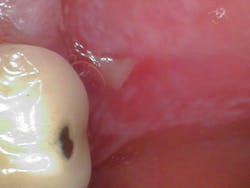

Clinical assessment revealed generalized ulcerated lesions intraorally, primarily focused on the buccal mucosa (figures 1 and 2). Furthermore, the tongue was coated with a white plaque-like layer.

In this particular case, the lesions had taken on an ulcerative form and, at first assessment, appeared like canker sores or aphthous ulcers. As the patient’s care continued over time (as she was seen for follow-up appointments), the lesions converted to the nonpainful reticular form. The patient reports flare-ups now and then, which are dependent on stress levels and the overall state of her body.